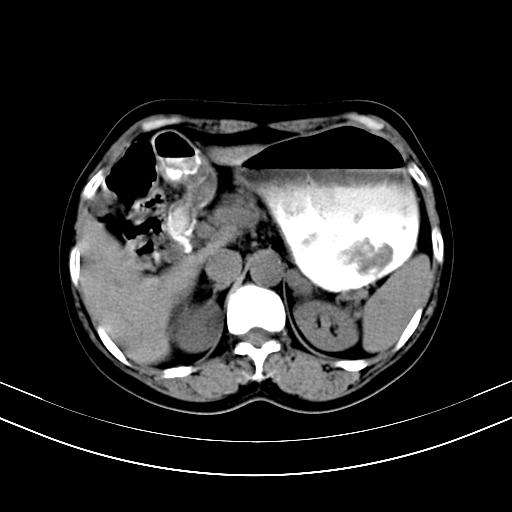

标题: CT12767:肝脏病变请会诊

补充强化片

胃内见充盈缺损,建议行胃镜病理检查,如果胃内无占位,则肝内考虑左叶、尾叶为包膜型肝癌,如有则考虑为转移瘤

胃内的充盈缺损,当时让患者俯卧位在扫描一下就 好了,当然最好是增强扫描,肝脏的病灶平扫很难定性,可以考虑是肝癌·血管瘤·转移瘤!

胃内见充盈缺损,建议行胃镜病理检查,如果胃内无占位,则肝内考虑左叶、尾叶为包膜型肝癌,如有则考虑为转移瘤,左侧肾上腺 明显增大,成结节改变,本人考虑转移瘤可能性大。

胃内的充盈缺损因胃壁不厚,我个人考虑为胃内残留物。肝左叶及尾叶病灶,我首先考虑血管瘤,其次为肝癌。(尾叶的更低密度区太规整)

肝脏左叶和尾叶均见略低密度影,尾叶病变内见坏死?其边界清晰,形态规整1血管瘤,2肝癌待排

胆囊内见一略高密度影,息肉?

1.肝左叶及尾叶占位建议增强2.肝硬化

肝脏左叶和尾叶均见略低密度影,尾叶病变内见坏死?其边界清晰,形态规整1血管瘤,2肝癌待排3建议增强。

胃内充盈缺损考虑为胃内存留物,肝左叶和尾状叶两个病灶,均为低密度,建议增强。

考虑:胃体小弯侧胃癌(或平滑肌瘤恶化或平滑肌肉瘤)伴肝转移,左侧肾上腺转移不除外.

胃内充盈缺损考虑为肿瘤,肝尾叶及左叶肿块考虑转移瘤

胃癌肝内转移及肾上腺转移。

胃窦部占位伴肝及左肾上腺转移可能大,建议增强扫描。

肝脏左叶和尾叶均见略低密度影,尾叶病变内见坏死?其边界清晰,形态规整1血管瘤,2肝癌待排3建议增强或结合临床及超声与实验室检查

肝左叶及尾叶低密度灶,增强有渐进性明显强化,考虑血管瘤。胃内“充缺”首先要排除异物(食物),变换体位可鉴别。增强时机抓的不好,还应该有延时像。

谢谢楼主的增强片子,平扫没发现左侧肾上腺的问题很不好意思,可惜片子只有门脉期,所以还只有猜,肝脏的病灶在门脉期部分强化,首先考虑为血管瘤(其他的用一种病不好解释)胃要喝水就好了现在不好说是否有问题,左肾上腺的问题考虑是肿瘤。

做了增强后,可以明确胃是没有肿瘤的,肾上腺也没有肿瘤.肝左叶的病灶首先考虑血管瘤,应该再延迟,肝尾状叶的病灶仍不能排除肝癌的可能性.